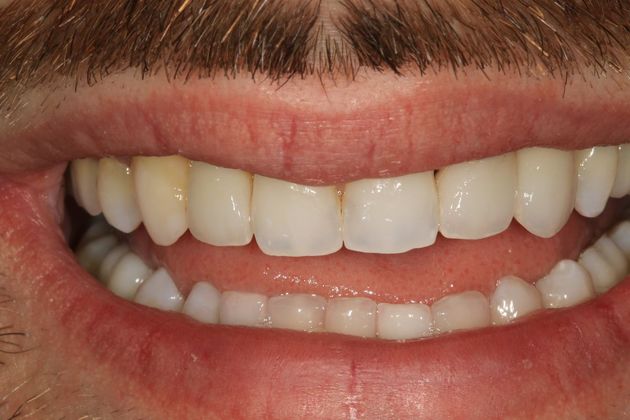

Full mouth rehabilitation. This 20 year old patient had emigrated from Bosnia only a few years earlier with his mother and two sisters after his father had perished in the Bosnian/Serbian conflict. He had severe hereditary dental dysplasia, with multiple retained baby teeth where permanent teeth never formed. He had a total of nine missing teeth, and the teeth that were present were not in their correct positions, leading to a poor bite relationship and multiple large gaps throughout his mouth. He was embarrassed to smile and wanted to know what could be done. His was a very complex case requiring Smile design and; the services of an oral surgeon to take out the baby teeth and strategically place implants at different times of his treatment, an orthodontist to level, straighten and create the proper size spaces for the placement of nine implants, gum sculpting, whitening, and the placement of fillings and crowns on natural teeth, and crowns on the nine implants. It took some time, but he got a great result and the resulting confidence has helped him go to college, get a better job and have a social life! Procedures: Smile design, oral surgery and implant placement, orthodontics, gum lift, whitening, fillings and crowns. TESTIMONIAL:" Dr. Balloch is a very skilled, compassionate and empathetic dentist who develops a personal relationship with his patients. He is (by far) the best dentist that I have experienced in my 85 years. His dental and office staff are equally friendly and professional. Dr.Balloch definitely exceeded my expectations. I highly recommend!"